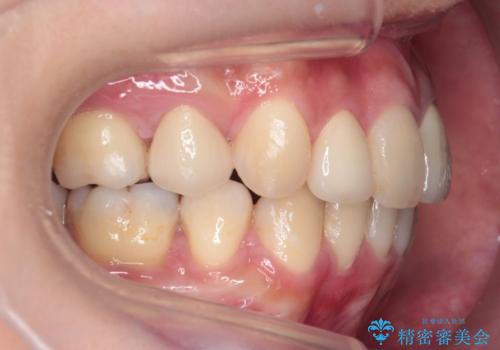

重度のがたつき 矯正治療+セラミック治療で綺麗な歯並びに 矯正専門では難しい治療

乳歯が残存しており、また左上の犬歯もずれて生えてきていました。

矯正治療で歯並びを治した後、乳歯を抜いたところにブリッジを入れています。

左上の奥歯はすれ違っていたためそのかみ合わせも整えています。

歯を抜いて治療を行ったため、Eラインが整った形で治療ができました。口が断然閉じやすくなっています。